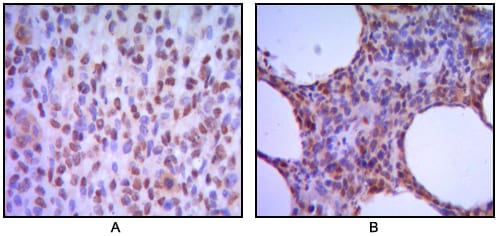

分类: 科研抗体货号: 30048别名: MUM-1; EXPAND1; HSPC211; FLJ14868; FLJ22283; MGC131891; MGC163315; MUM1应用: IHC反应种属: Human

分类: 科研抗体货号: 30047别名: GF1; GF-1; NFE1; XLTT; ERYF1; GATA-1; GATA1应用: WB,IHC,IF反应种属: Human